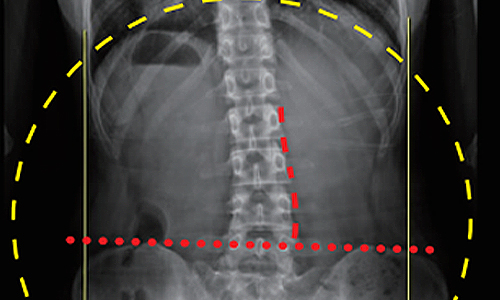

• 10대 학생

치료기간 1.5개월

BEFORE

AFTER